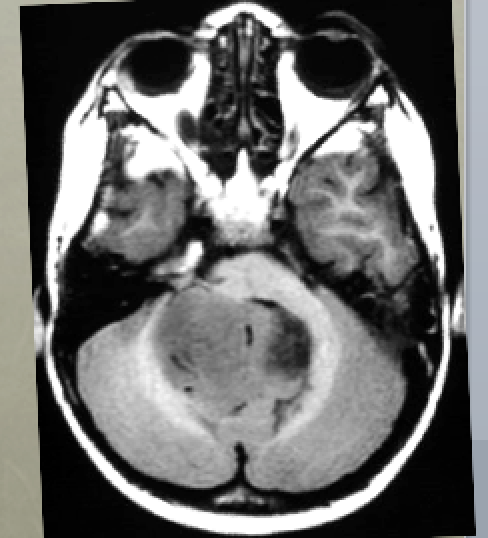

5yo with ataxia, vomiting, and headache

Differential diagnoses and most likely diagnosis?

Differential:

Ependymoma

Juvenile pilocytic astrocytoma

Medulloblastoma.

Most likely:

Ependymoma - 4th ventricle mass, expanding through Magendie and Luschka foramina. Can calcify and have cystic components. Nonhomogeneous contrast enhancement.